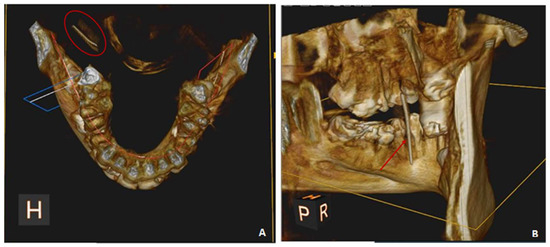

5. Case Report